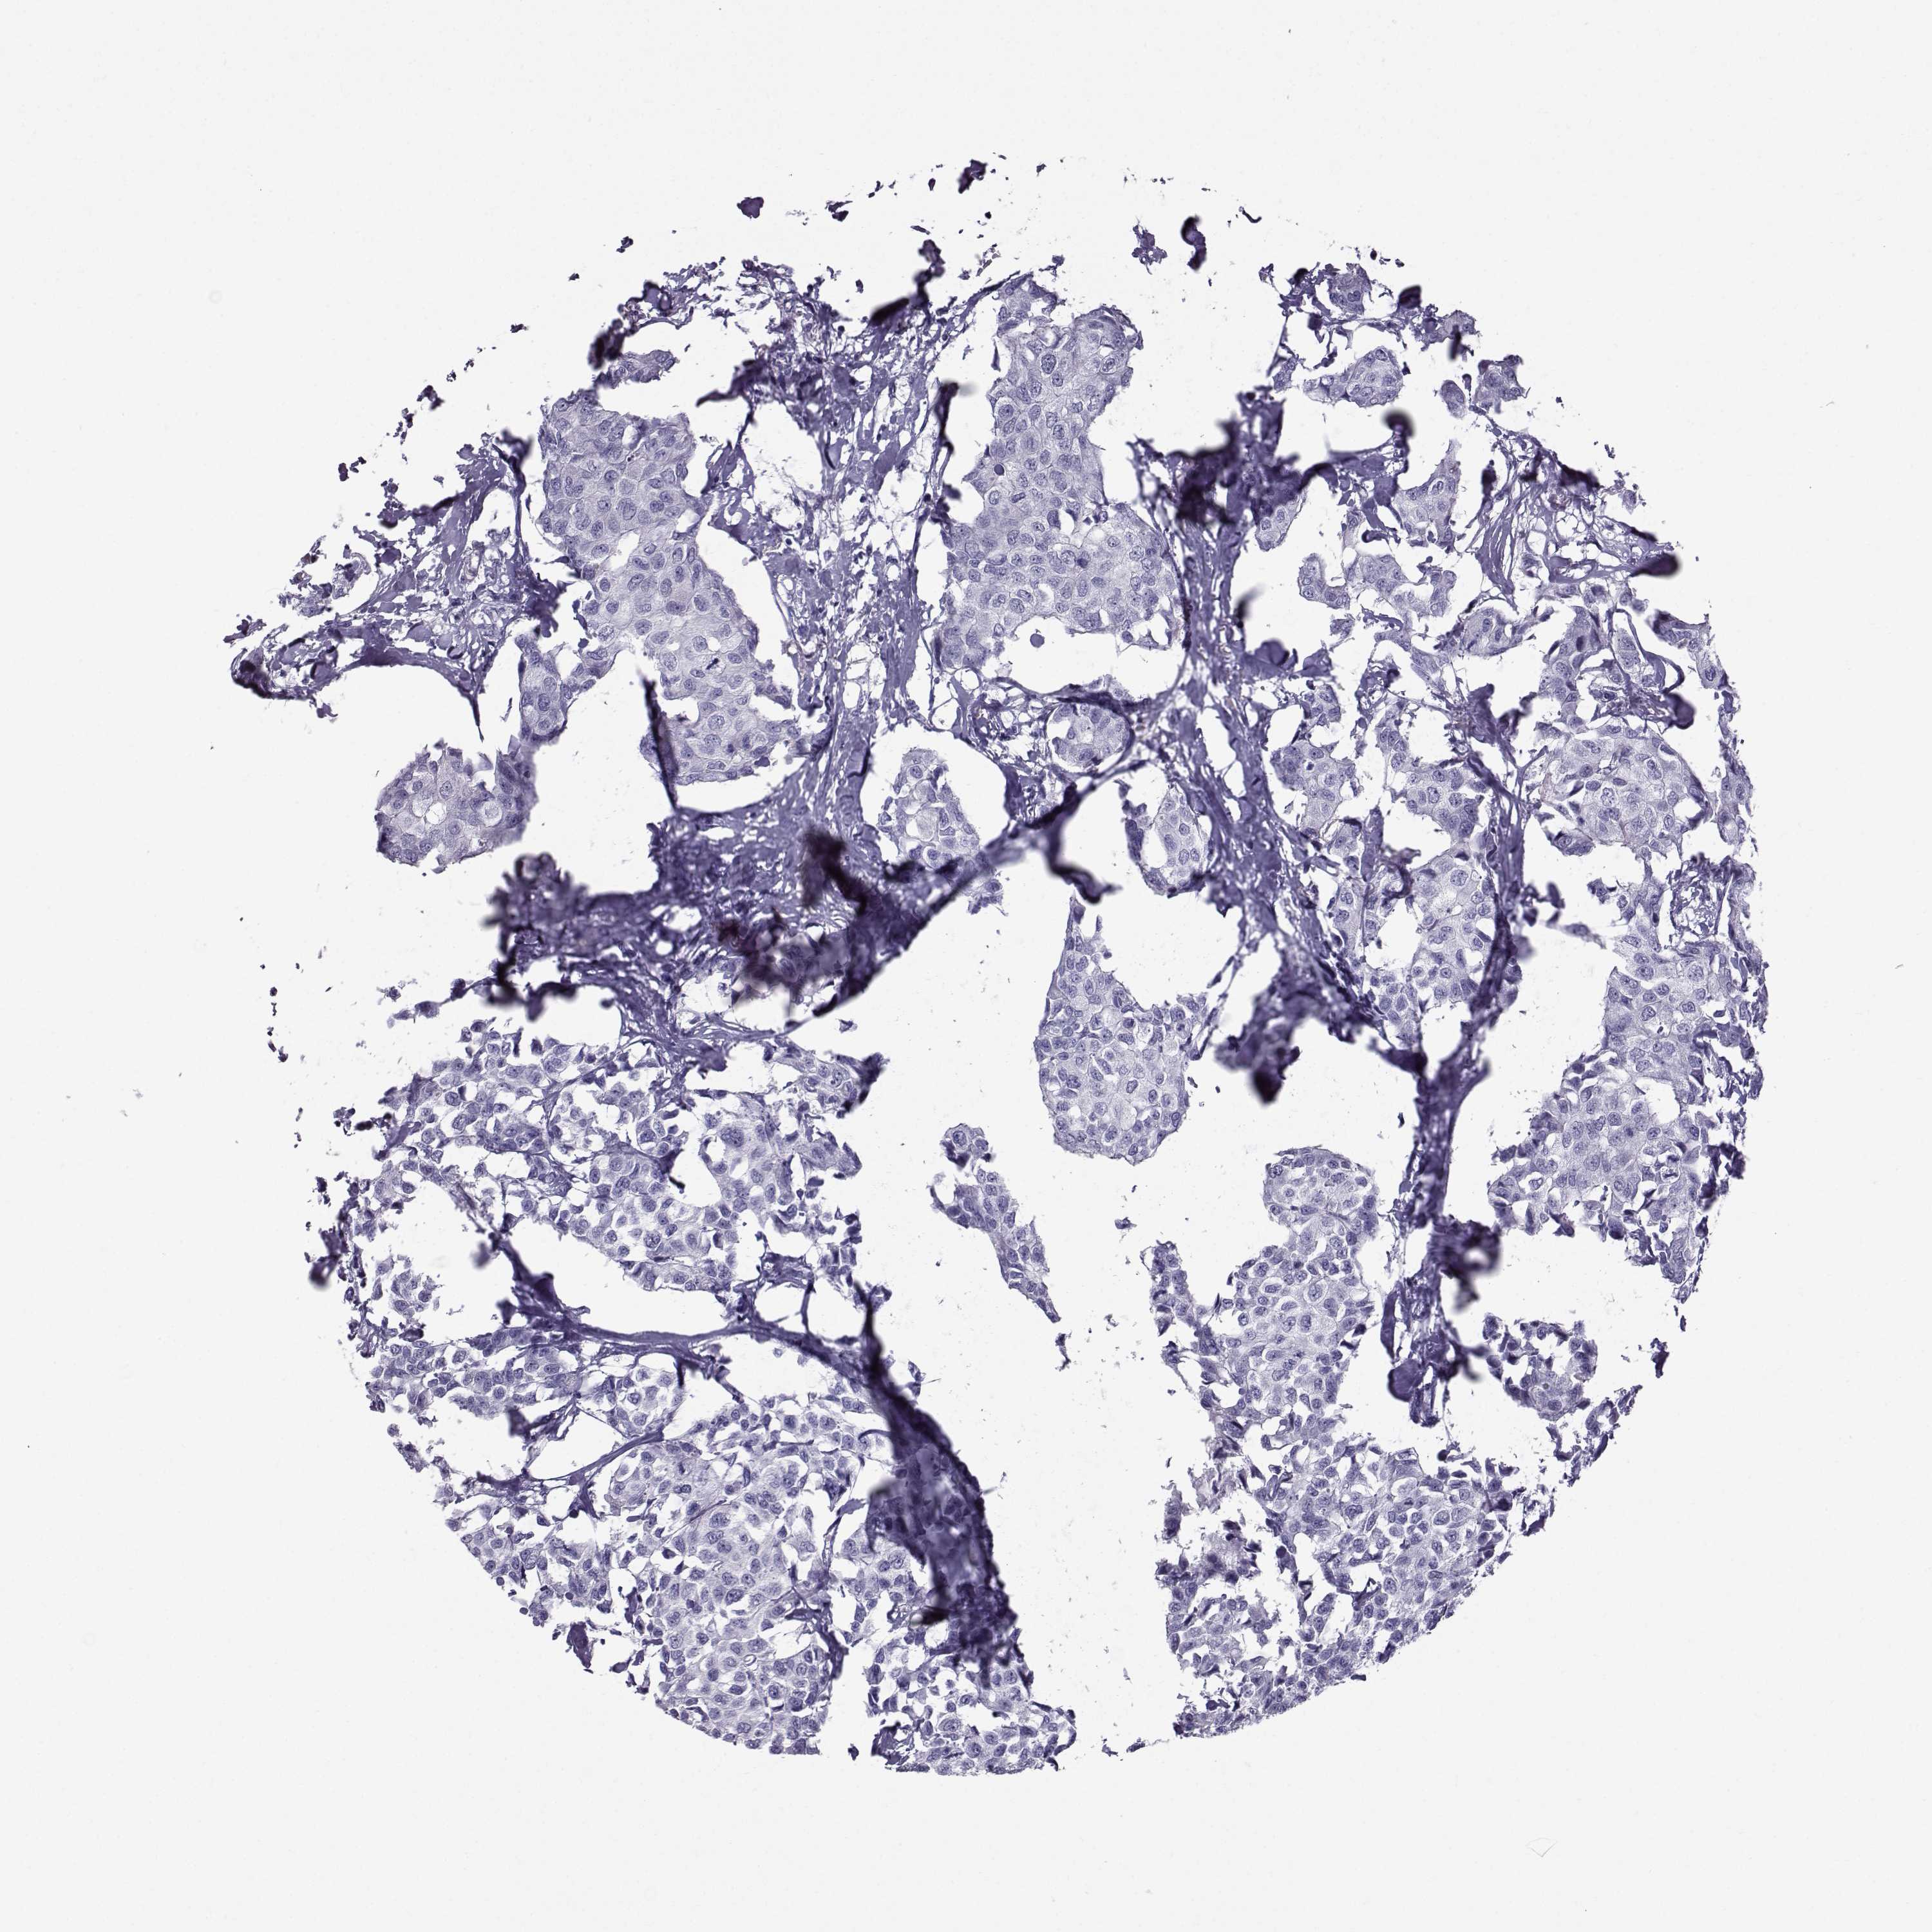

Breast cancer

Human cancer